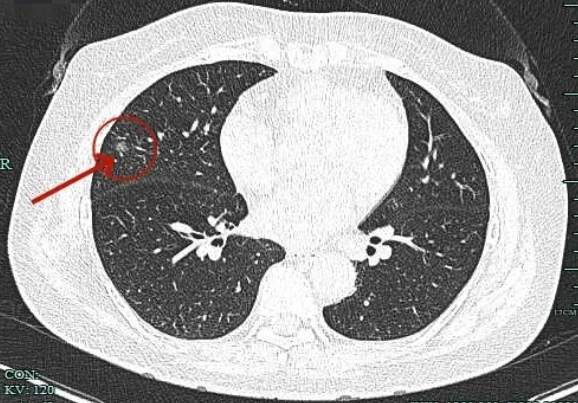

影像展示与分析:

病灶出现,磨玻璃密度,轮廓较清,此层示见显著实性成分。